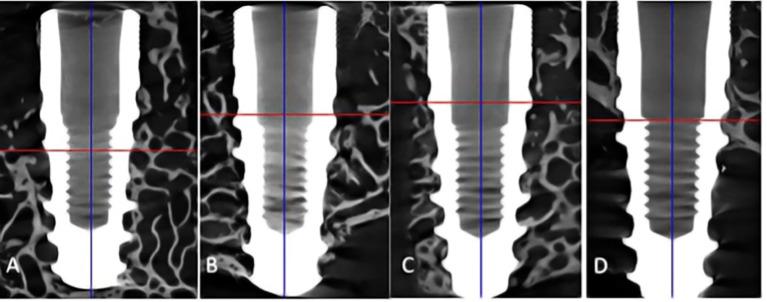

Hydroxyapatite used as a coating for titanium dental implants reduces the time required for osseointegration. Platelet-rich fibrin (L-PRF) releases growth factors and cytokines, enhancing tissue healing and bone regeneration. This study aimed to evaluate histologically, histomorphometrically, and by microcomputed tomography an implant surface coated with nanostructured hydroxyapatite (HAnano), in comparison with a double acid-etched (DAA) surface, both with and without peri-implant grafting with L-PRF, installed in over-instrumented sites in a low-density bone. Five adult sheep (2-4 years old) received twenty 3.5 × 10 mm implants in the iliac crest. Bone-to-implant contact (BIC) and bone-occupied area fraction (BAFo) were evaluated histomorphometrically after an 8-week experimental period. Brown-Forsyth analysis of variance (ANOVA) and Welch's ANOVA test did not identify significant differences between the experimental groups. On average, BIC ranged from 44% (HAnano + L-PRF) to 63% (DAA + L-PRF). µCT analysis revealed that bone volume density in the peri-implant region ranged from 26% (HAnano + L-PRF) to 39% (DAA). No statistically significant differences were observed between the groups. Both implant surfaces studied allowed osseointegration in low bone density sites, independently of peri-implant grafting with L-PRF, after 8 weeks of implantation. While this model provided controlled conditions for evaluating early-stage osseointegration, the absence of functional loading and the relatively short follow-up period should be considered when extrapolating the findings to clinical applications. Future studies should assess these variables under load-bearing conditions with extended observation periods. All the sheep in this study remained alive.

用作牙科钛植入物涂层的羟基磷灰石可减少骨结合所需的时间。富血小板纤维蛋白(L-PRF)可释放生长因子和细胞因子,促进组织愈合和骨再生。本研究旨在通过组织学、组织形态计量学以及微计算机断层扫描,评估一种涂覆有纳米结构羟基磷灰石(HAnano)的植入物表面,与双重酸蚀(DAA)表面相比,在低密度骨的过度预备部位植入时,有无L-PRF进行种植体周围植骨的情况。五只成年绵羊(2 - 4岁)在髂嵴植入20枚3.5×10毫米的植入物。在8周的实验期后,通过组织形态计量学评估骨与植入物接触(BIC)和骨占据面积分数(BAFo)。Brown-Forsyth方差分析(ANOVA)和Welch's ANOVA检验未发现实验组之间存在显著差异。平均而言,BIC范围为44%(HAnano + L-PRF)至63%(DAA + L-PRF)。µCT分析显示,种植体周围区域的骨体积密度范围为26%(HAnano + L-PRF)至39%(DAA)。各实验组之间未观察到统计学上的显著差异。植入8周后,所研究的两种植入物表面均可在低骨密度部位实现骨结合,与是否使用L-PRF进行种植体周围植骨无关。虽然该模型为评估早期骨结合提供了可控条件,但在将研究结果外推至临床应用时,应考虑缺乏功能负荷以及随访期相对较短的问题。未来的研究应在负重条件下并延长观察期来评估这些变量。本研究中的所有绵羊均存活。